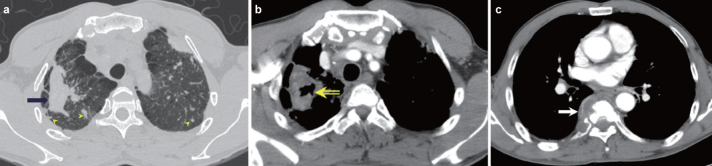

FIG. 3. a–c.

TB appearing as a cavitating mass in a 57-year-old man with pneumoconiosis. A 5-cm conglomerated mass (arrow) in the right upper lobe and multiple small nodules (arrowheads) bilaterally in the high-resolution CT scan (a) taken 10 months before admission. This patient had been given a diagnosis of coal worker’s pneumoconiosis 5 years prior. On admission, the mediastinum window setting (b) showed cavitation (open arrow) of the mass in the right upper lobe with growth of the mass (6.5 cm in diameter) and the osteolytic T7 (c, arrow) with paravertebral soft tissue formation on admission. CT-guided biopsy was performed to differentiate between lung cancer with bone metastasis versus pulmonary TB with spine involvement. The final diagnosis was tuberculosis. This case illustrates cavitation and growth of progressive massive fibrosis after infection with M. tuberculosis

With regard to coexisting pulmonary diseases, six patients had coexisting emphysema. This included one patient with a nodule and one patient with a mass, while the remaining four cases appeared in patients with CT features of nonsegmental consolidation (Figure 1). Usual interstitial pneumonia (UIP) was present in one case with a mass and in four cases with consolidative TB lesions (Figure 2). Pneumoconiosis was present in two cases with mass lesions (Figure 3). There were no significant coexisting lung diseases in the other patients.